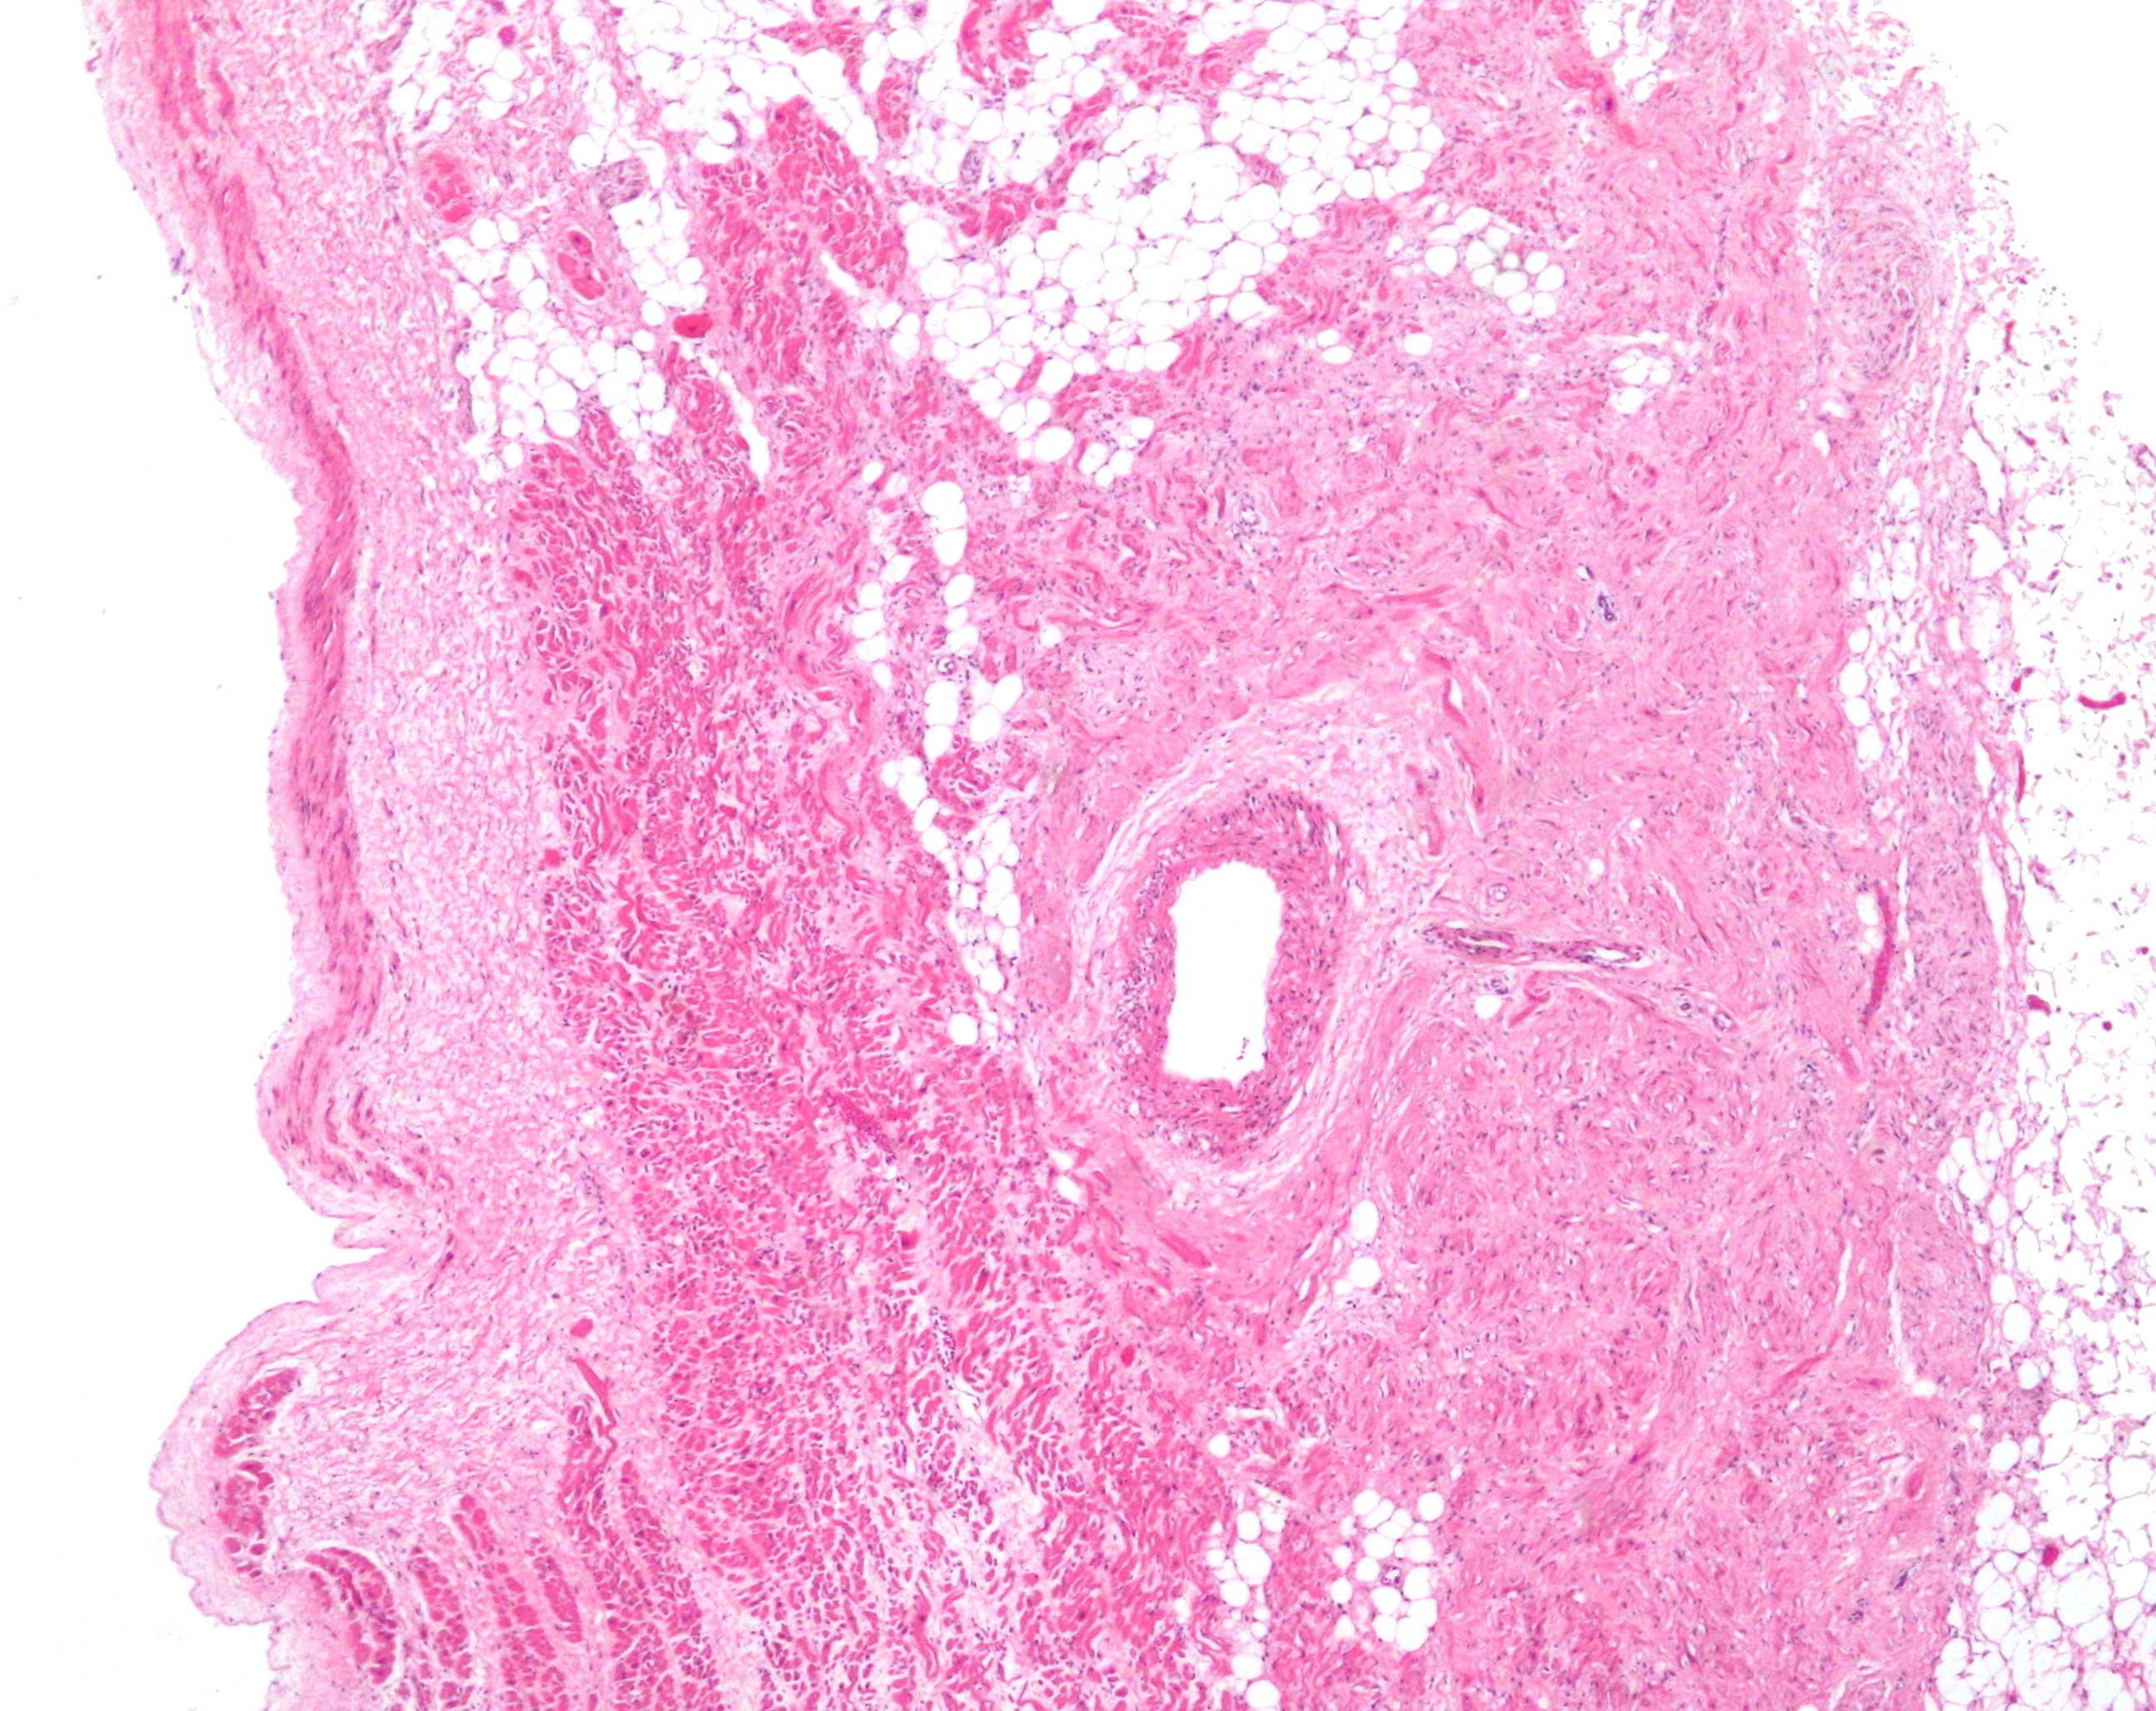

굴심방결절 세포는 신경, 혈관, 콜라겐, 지방을 포함하는 결합 조직 그물망 구조 내에 퍼져 있다.[29] 굴심방결절 세포를 직접 둘러싸고 있는 것은 결절주변세포(paranodal cells)이다.[29] 결합 조직은 결절주변세포와 함께 굴심방결절 세포를 나머지 심방과 절연시켜 심방 세포의 전기적 활동이 굴심방결절 세포에 영향을 미치는 것을 방지한다.[29] 굴심방결절 세포는 주변 심방 세포보다 작고 옅으며, 평균 직경은 약 8μm이고 길이는 20~30μm 정도이다.[33] 심방 세포와 달리 굴심방결절 세포에는 더 적은 수의 미토콘드리아와 근섬유가 있고, 근소포체가 더 작아 수축에는 덜 적합하다.[34]